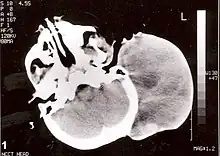

Non-contrast CT scan of head showing a large mass without any intracranial extension. The diagnosis was post-auricular congenital alveolar rhabdomyosarcoma. | |